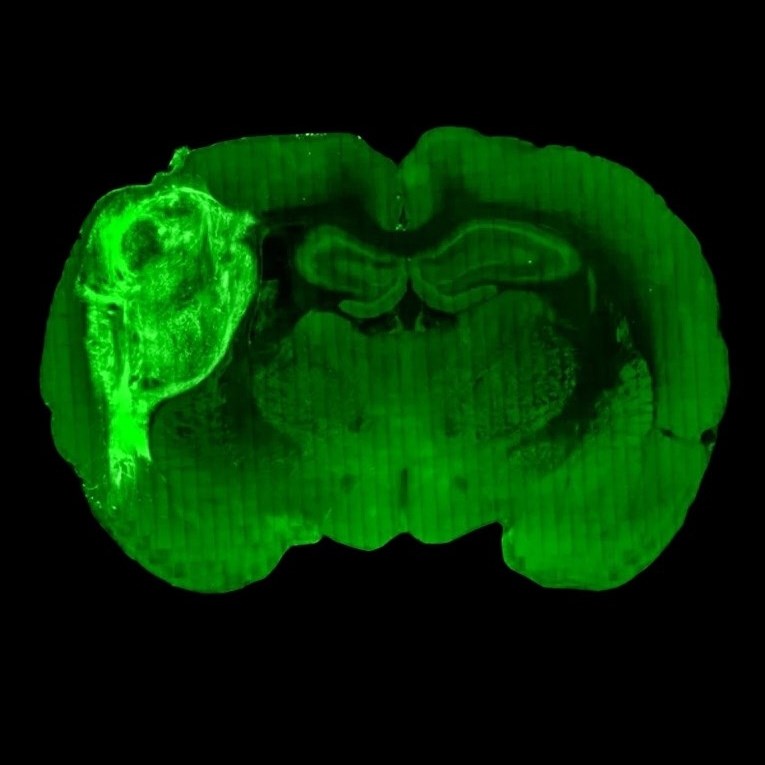

Štakoru usađen minijaturni ljudski mozak

Naučnici sa Stanforda objavili su da su nakupine ljudskih stanica, poznate kao “organoidi”, izrasle u milijune novih neurona i spojile se u nove živčane sustave povezane sa sustavima štakora. Minijaturne strukture nalik na ljudski mozak presađene u štakore povezale su se s mozgovima štakora, slale su signale i reagirale na podražaje iz okoline koje hvataju brkovi štakora te čak mijenjale njihovo ponašanje.

Ovi nalazi trebali bi omogućiti istraživanja različitih neurodegenerativnih i neuropsihijatrijskih poremećaja u ljudskom mozgu. Voditelj istraživanja Sergiu Pasca, neuroznanstvenik sa Stanforda, objasnio je da su on i njegovi kolege štakorima transplantirali ljudske neurone kako bi upoznali biologiju koja se nalazi u pozadini autizma, shizofrenije i drugih razvojnih poremećaja.